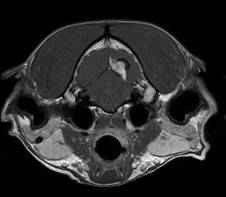

Científicos daneses han utilizado la Tomografía Computarizada (TC) y la Resonancia Magnética (RM) para investigar los órganos internos de los animales, entre los que se encuentran caimanes, serpientes y tarántulas.

Las imágenes revelaron, por primera vez de manera no invasiva, cómo una serpiente adapta sus órganos internos antes de una gran comida y durante la digestión, hasta que el alimento haya desaparecido por completo.

La nueva investigación, presentada el miércoles 30 de junio de 2010 en la Reunión Anual de la Sociedad para la Biología Experimental en Praga, mostró por primera vez todo el ciclo de digestión de una pitón birmana con las modernas técnicas de resonancia magnética y tomografía computarizada.

Se obtuvo la imagen digital de las pitones birmanas (Python molurus) antes de la ingestión de una rata y después de 2, 16, 24, 40, 48, 72 y 132 horas de la misma. La sucesión de imágenes reveló una progresiva desaparición del cuerpo de la rata, acompañada de una expansión global del intestino, la reducción de la vesícula biliar, y un aumento del 25% en el volumen del corazón.

El equipo utilizó una combinación de Tomografía Computarizada, que se adapta a los tejidos duros (huesos, dientes, caparazones, etc.) y Resonancia Magnética, más adecuada para los tejidos blandos, con el objetivo de visualizar las estructuras internas de los órganos y el sistema vascular.

Al elegir la correcta configuración de contraste y de intensidad de luz durante el proceso de exploración, los científicos fueron capaces de resaltar determinados órganos y los hicieron aparecer en diferentes colores.